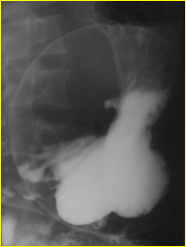

Grande ulcere antral et

bourerelet oedemateux . Lesion ulceriforme de type 3

|